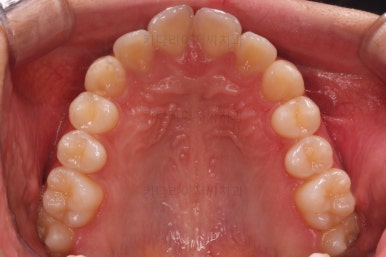

부산교정 키다리아저씨치과에 처음 내원하셨을 당시의 입안 모습과 X-ray 사진입니다.

초진 시 다른 부위들 사진입니다.

약간의 주걱턱 느낌에 약간의 돌출감, 전반적인 치열의 가지런한 느낌은 나쁘지 않았지만 약간의 불량한 교합상태였어요.